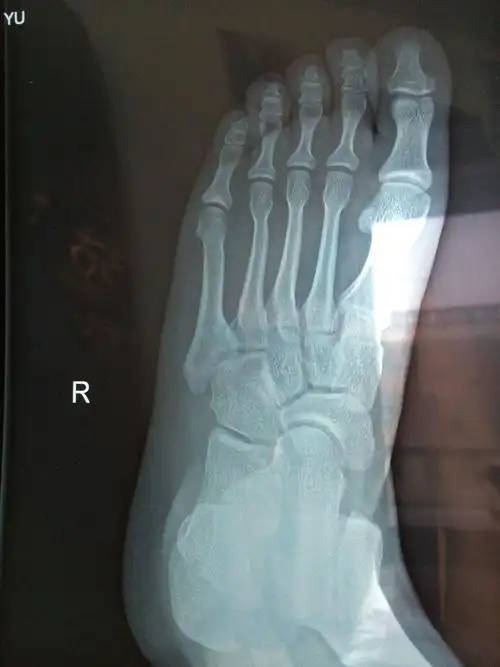

我的左脚摔伤了,去医院拍了个片子,医生说我的脚面上骨折了.